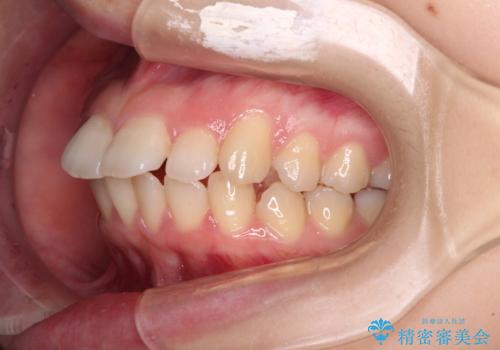

- 上下の前歯が突出しており、口が閉じにくいとのことで来院された患者様です。

上下前歯が著しく前突している状態であったので、上下左右の第1小臼歯4本を抜歯し、ワイヤー装置にて矯正治療を行うこととしました。